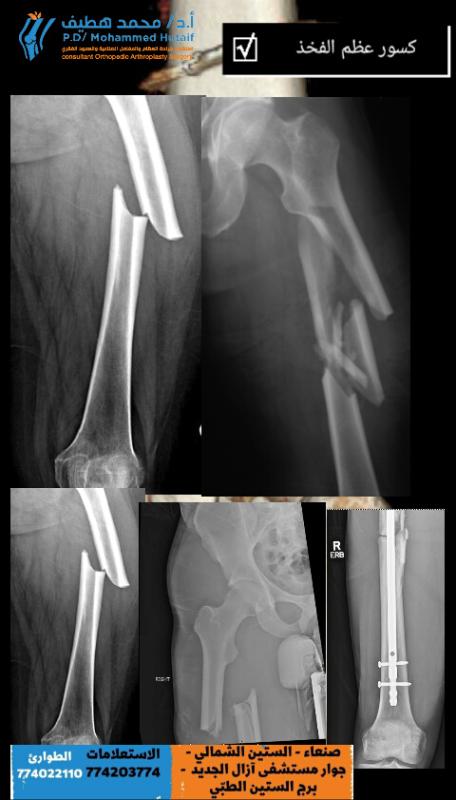

كسور عظم الفخذ هي إصابات عالية الطاقة لعظم الفخذ مرتبطة بإصابات مهددة للحياة (رئوية ودماغية) وكسور عنق الفخذ المماثل. يتم تشخيص كسور عظم الفخذ بالتصوير الشعاعي لعظم الفخذ وكذلك الورك ل…